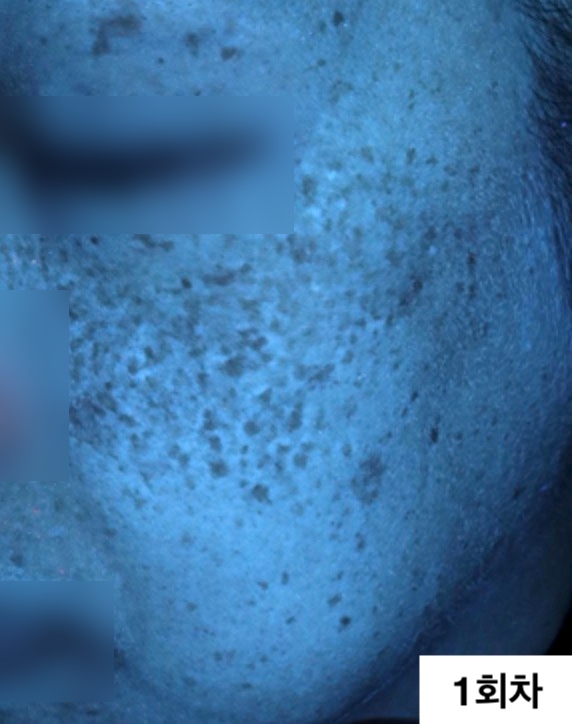

자외선광 1회차 / 10회차

2024.12.24